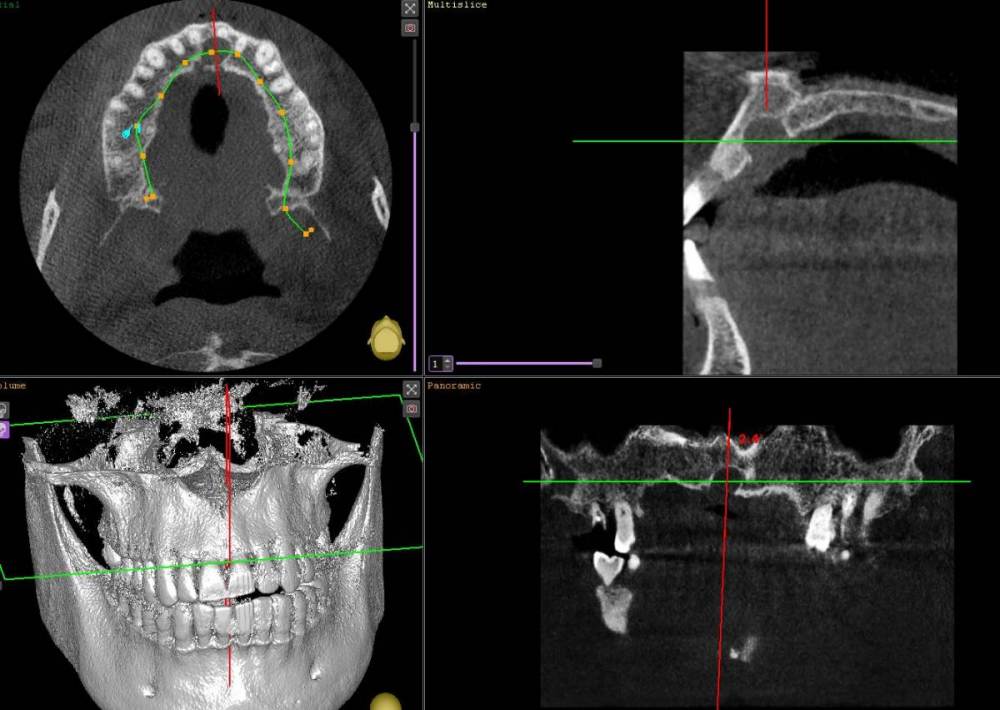

nevlvi Опубликовано 2 августа, 2021 Поделиться Опубликовано 2 августа, 2021 Здравствуйте, обнаружил на КТ вот такое образование. Полагаю это глобуломаксиллярная киста, размер 8 *6,5 * 7мм. Симптоматики нет. Может быть кто-то стыкался с подобным. Интересует: 1. Тактика лечения 2.При экскохлеации возможно ли задеть резцовый канал? Ссылка на комментарий

АнтонТЛТ Опубликовано 3 августа, 2021 Поделиться Опубликовано 3 августа, 2021 Больше похоже на кисту резцового канала 5 Ссылка на комментарий